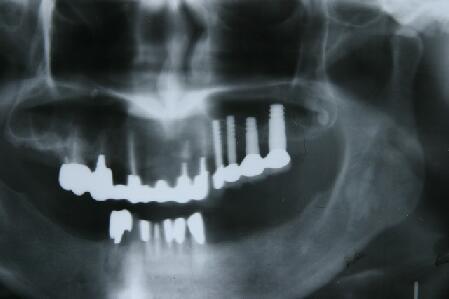

4ヵ月後に最終かぶせ物をしてメンテナンスへ

4ヶ月して、当初1~3ミリしか存在しなっかた骨が7~12ミリ程度(部位によって違う)になり 予定通り最終かぶせ物(メタルボンドポーセレン)を装着

8ヵ月後のエックス線写真

(注)上のエックス線写真の一番左に見える5本目、前歯部位のインプラントは奥歯の完成後、 埋入手術を行ったものです

・全体の写るエックス線写真よりこの小さなエックス線写真で見ほうが骨の出来方が良く分かる と思います。十分咬合に耐える、しっかりした骨が形成されています

・この新しいインプラントでは今までのインプラントのように複雑で、長い期間を必要とする上顎 洞への自家骨移植、人工骨添加は必要ないことがお分かりと思います